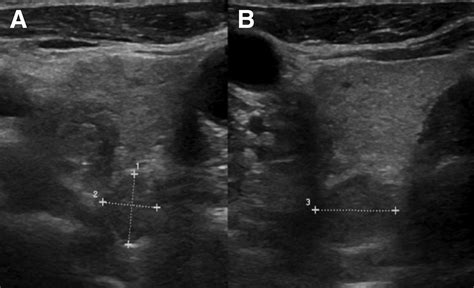

Interpreting the results of parathyroid gland sonography requires expertise in radiology and endocrinology. The images obtained during the procedure are analyzed for several key features:

• Size and shape of the parathyroid glands.

• Presence of any nodules or masses.

• Location of the parathyroid glands relative to the thyroid gland.

• Blood flow patterns within the glands, which can indicate the presence of tumors.

Abnormal findings may include enlarged parathyroid glands, the presence of adenomas, or other structural abnormalities. These findings are crucial for diagnosing conditions such as primary hyperparathyroidism, secondary hyperparathyroidism, and parathyroid carcinoma.